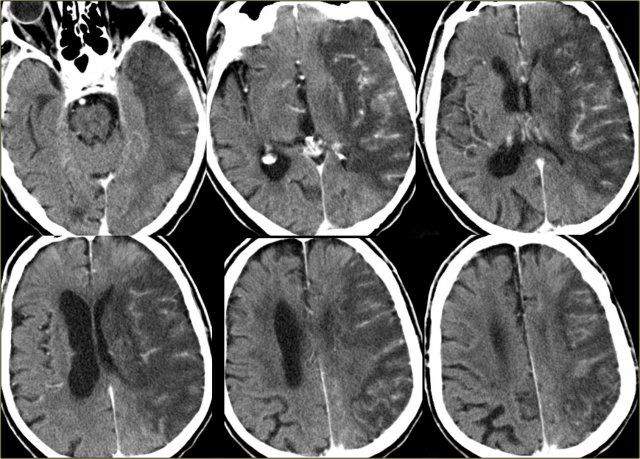

Hình ảnh CT và chuỗi xung T2W-gradient echo của nhồi máu xuất huyết giới hạn trong vùng tưới máu của các động mạch thấu kính – vân bên

Bên trái là hình ảnh nhồi máu xuất huyết trong vùng các nhánh thấu kính – vân xuyên sâu của MCA.

Bên trái là hình ảnh CT có thuốc cản quang của bệnh nhân bị nhồi máu trong vùng tưới máu của động mạch não giữa (MCA).

Có hiện tượng ngấm thuốc hồi não lan rộng (tưới máu xa xỉ).

Đôi khi hiện tượng tưới máu xa xỉ này có thể gây nhầm lẫn với hình ảnh ngấm thuốc của khối u.